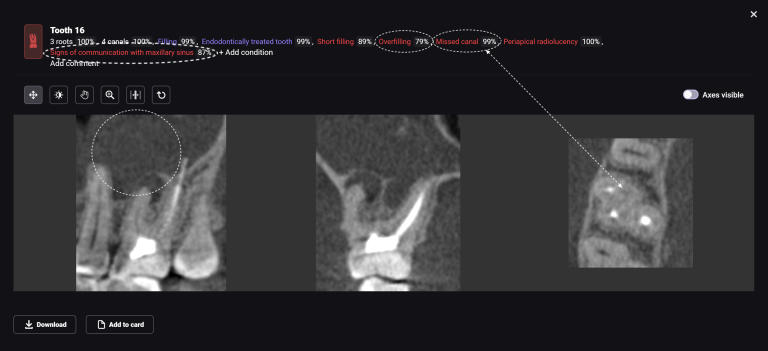

Diagnocat assists clinicians in implant treatment planning, both in guided surgery and in a classical approach. Let’s explore the capabilities of Diagnocat through a clinical case example of planning implant treatment for the replacement of missing teeth 17,16 (Universal 2,3)

The use of Diagnocat AI in planning implant treatment improves the accuracy and predictability of the procedure, allowing the clinician to achieve the best results for the patient